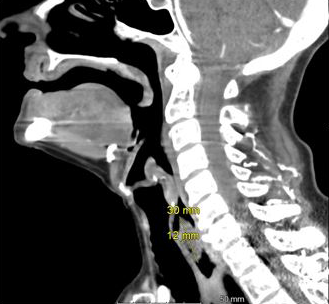

While opsoclonus-myoclonus-ataxis (dancing eye-dancing feet syndrome) may seem rare and complex, its early identification in the ED can be life‑altering. When faced with an unusual movement disorder a